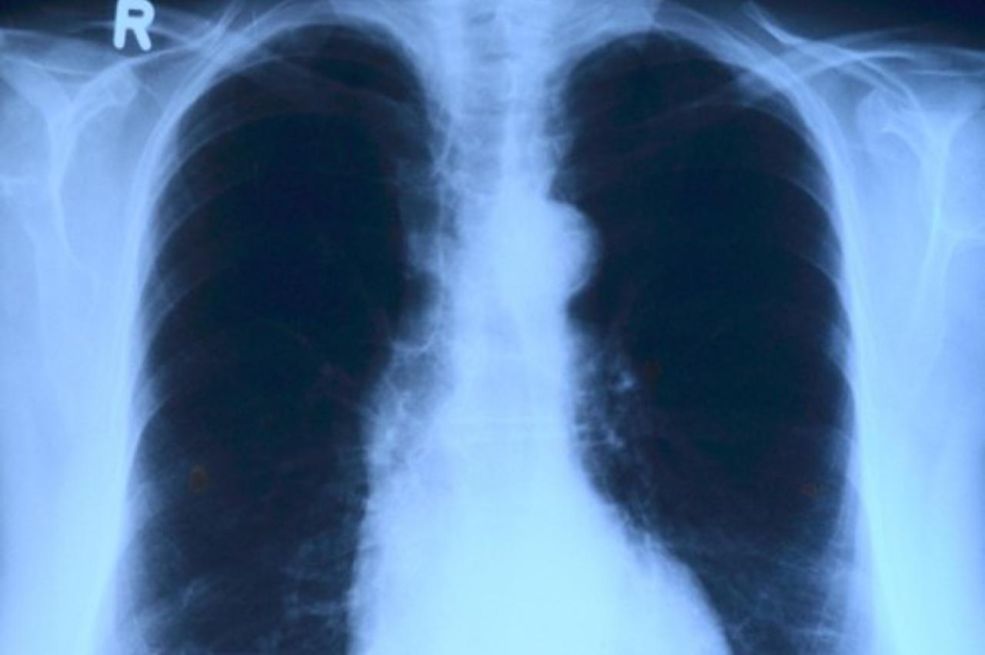

Prema podacima Agencije za zdravstvenu sigurnost Ujedinjenog Kraljevstva (UKHSA), u 2024. godini zabilježeno je 5490 slučajeva, što je porast od 13,6% u odnosu na 4831 slučaj u 2023. godini. Liječnici upozoravaju da mnogi građani dugotrajni kašalj pripisuju gripi ili Cov,idu-19, dok bi uzrok zapravo mogla biti tuberkuloza – bolest koja je nekada bila gotovo iskorijenjena, ali se sada ponovno širi u pojedinim dijelovima zemlje, prenosi Vecernji.hr. Tuberkuloza, uzrokovana bakterijom Mycobacterium tuberculosis, najčešće napada pluća, ali može zahvatiti i mozak, kralježnicu ili bubrege.

Simptomi uključuju uporan kašalj duži od tri tjedna (često s ispljuvkom ili krvlju), vrućicu, noćno znojenje, umor, gubitak težine i apetita. Ako se ne liječi, može uzrokovati trajna oštećenja pluća ili smrtonosne komplikacije poput meningitisa ili zatajenja organa, javlja Daily Mail.